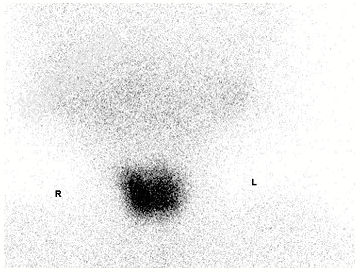

- [材料题] 3岁男童,行⁹⁹TcᵐO₄⁻甲状腺静态显像如图:

- 简答题1、请对该图进行描述。